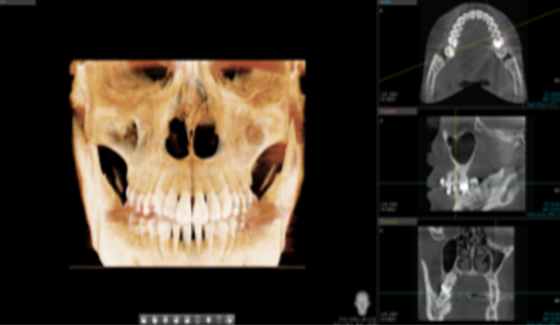

• 3D CT

치아, 잇몸뼈 골격까지 진단

실제 구강을 입체적으로 재현

3D 기술을 활용한 정확한 진단

Digital 01

• 정밀한 진단을 통한 체계적인 계획

치아뿌리 길이, 모양, 잇몸뼈의 두께와 밀도, 과잉치와 치아종 등 3D CT 정밀진단을 통해 환자의 치아 및 잇몸 상태를 고려한 치료계획을 세울 수 있습니다.